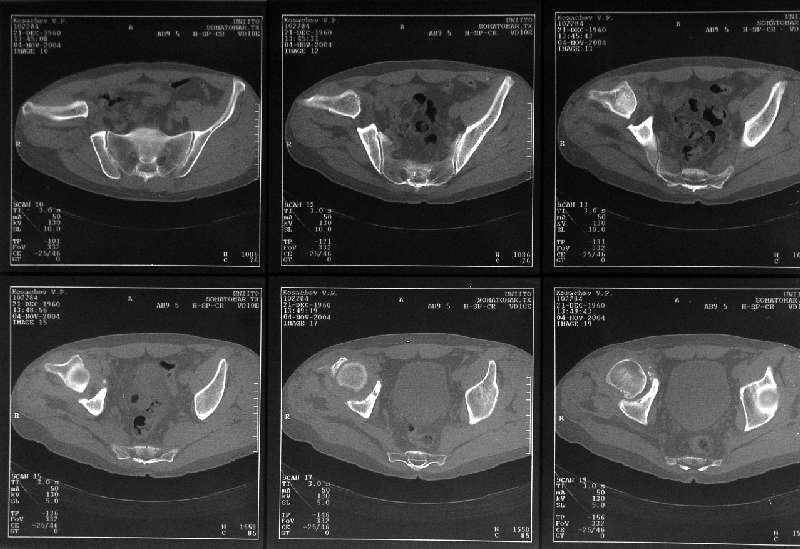

мужчина, 43 лет, получил травму в январе 2001 года. Лечился консервативно, в соседней области: скелетное вытяжение 6 недель, далее в кокситной гипсовой повязке 2 месяца. С декабря 2001 года ходит без дополнительной опоры, с компенсацией имеющегося укорочения - 4 сантиметра. С марта этого года беспокоят боли, усиливающиеся после умеренной физической нагрузки, возникающие в задних отделах таза и переходящие в область тазобедренного сустава. По данным ретгенографии и компьютерной томографии у больного имеется несросшийся высокий двухколонный перелом вертлужной впадины. Заранее спасибо.